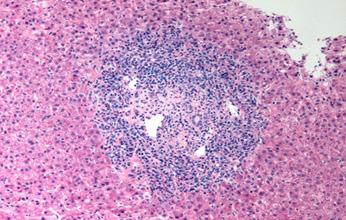

La miocarditis es una enfermedad inflamatoria del músculo cardíaco, diagnosticada mediante biopsia endomiocárdica.

Biopsia de miocardio:

Mediante cateterismo cardíaco y biopsia asistida por resonancia magnética

Se indica en casos de Insuficiencia cardíaca de nueva aparición, arritmias graves y resistencia al tratamiento